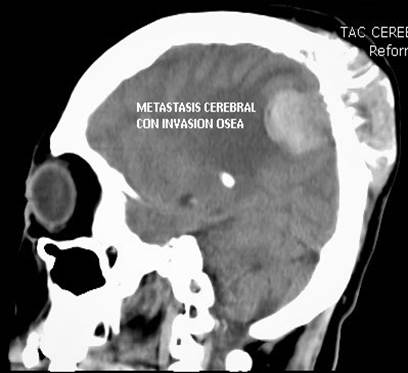

CASO 2 (METASTASIS CEREBRAL)

Paciente de 68 años de edad, que ingresa referida de otra institución por presentar más tumoral en región occipital derecha de gran tamaño dura muy adherida, dolorosa con circulación colateral; paciente desorientada en tiempo y espacio, irritable y poco colaborativa, en algunas ocasiones ha presentado convulsiones tónico clónicas. Además, presenta masa cervical voluminosa, a nivel tiroidea, dura, adherida a estructura aéreas y vasculares.

Se toma biopsia con aguja gruesa de lesión tumoral cervical y tumoración occipital encontrando carcinoma papilar variante oncocitica. Paciente fue tratada por el departamento de oncología clínica en forma paliativa y con Sorafenib por no haber mejoría con radio-yodo.

Ilustración 6 Metástasis ósea y cerebral con gran vascularización.

![]() |

Fuente: Hospital de Especialidades Guayaquil “Doctor Abel Gilbert Pontón”.

Autor: Dr. Fernando Moncayo A.

Ilustración 8 Ca de tiroides y metástasis cerebral.